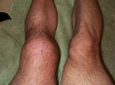

Diz kapağında ağrı çeken biri olarak, birkaç yöntemle bu durumu hafifletebilirsiniz. Öncelikle, dinlenmek ve dizinizi aşırı yormaktan kaçınmak önemlidir. Buz uygulaması, şişliği ve ağrıyı azaltmada etkili bir yöntemdir. Buzu doğrudan cildinize uygulamaktan kaçının; bir havluya sararak 15-20 dakika boyunca dizinize uygulayabilirsiniz. Bu işlemi günde birkaç kez tekrarlamak faydalı olabilir.

Eğer diz ağrınız aşağıdaki belirtilerle birlikteyse mutlaka bir doktora başvurmalısınız: Şiddetli ağrı, dizde şişme veya sertlik, yürümekte zorluk, dizin kilitlenmesi veya herhangi bir yaralanma sonrası ortaya çıkan ağrı. Bu durumlar, daha ciddi bir sağlık sorununun habercisi olabilir.